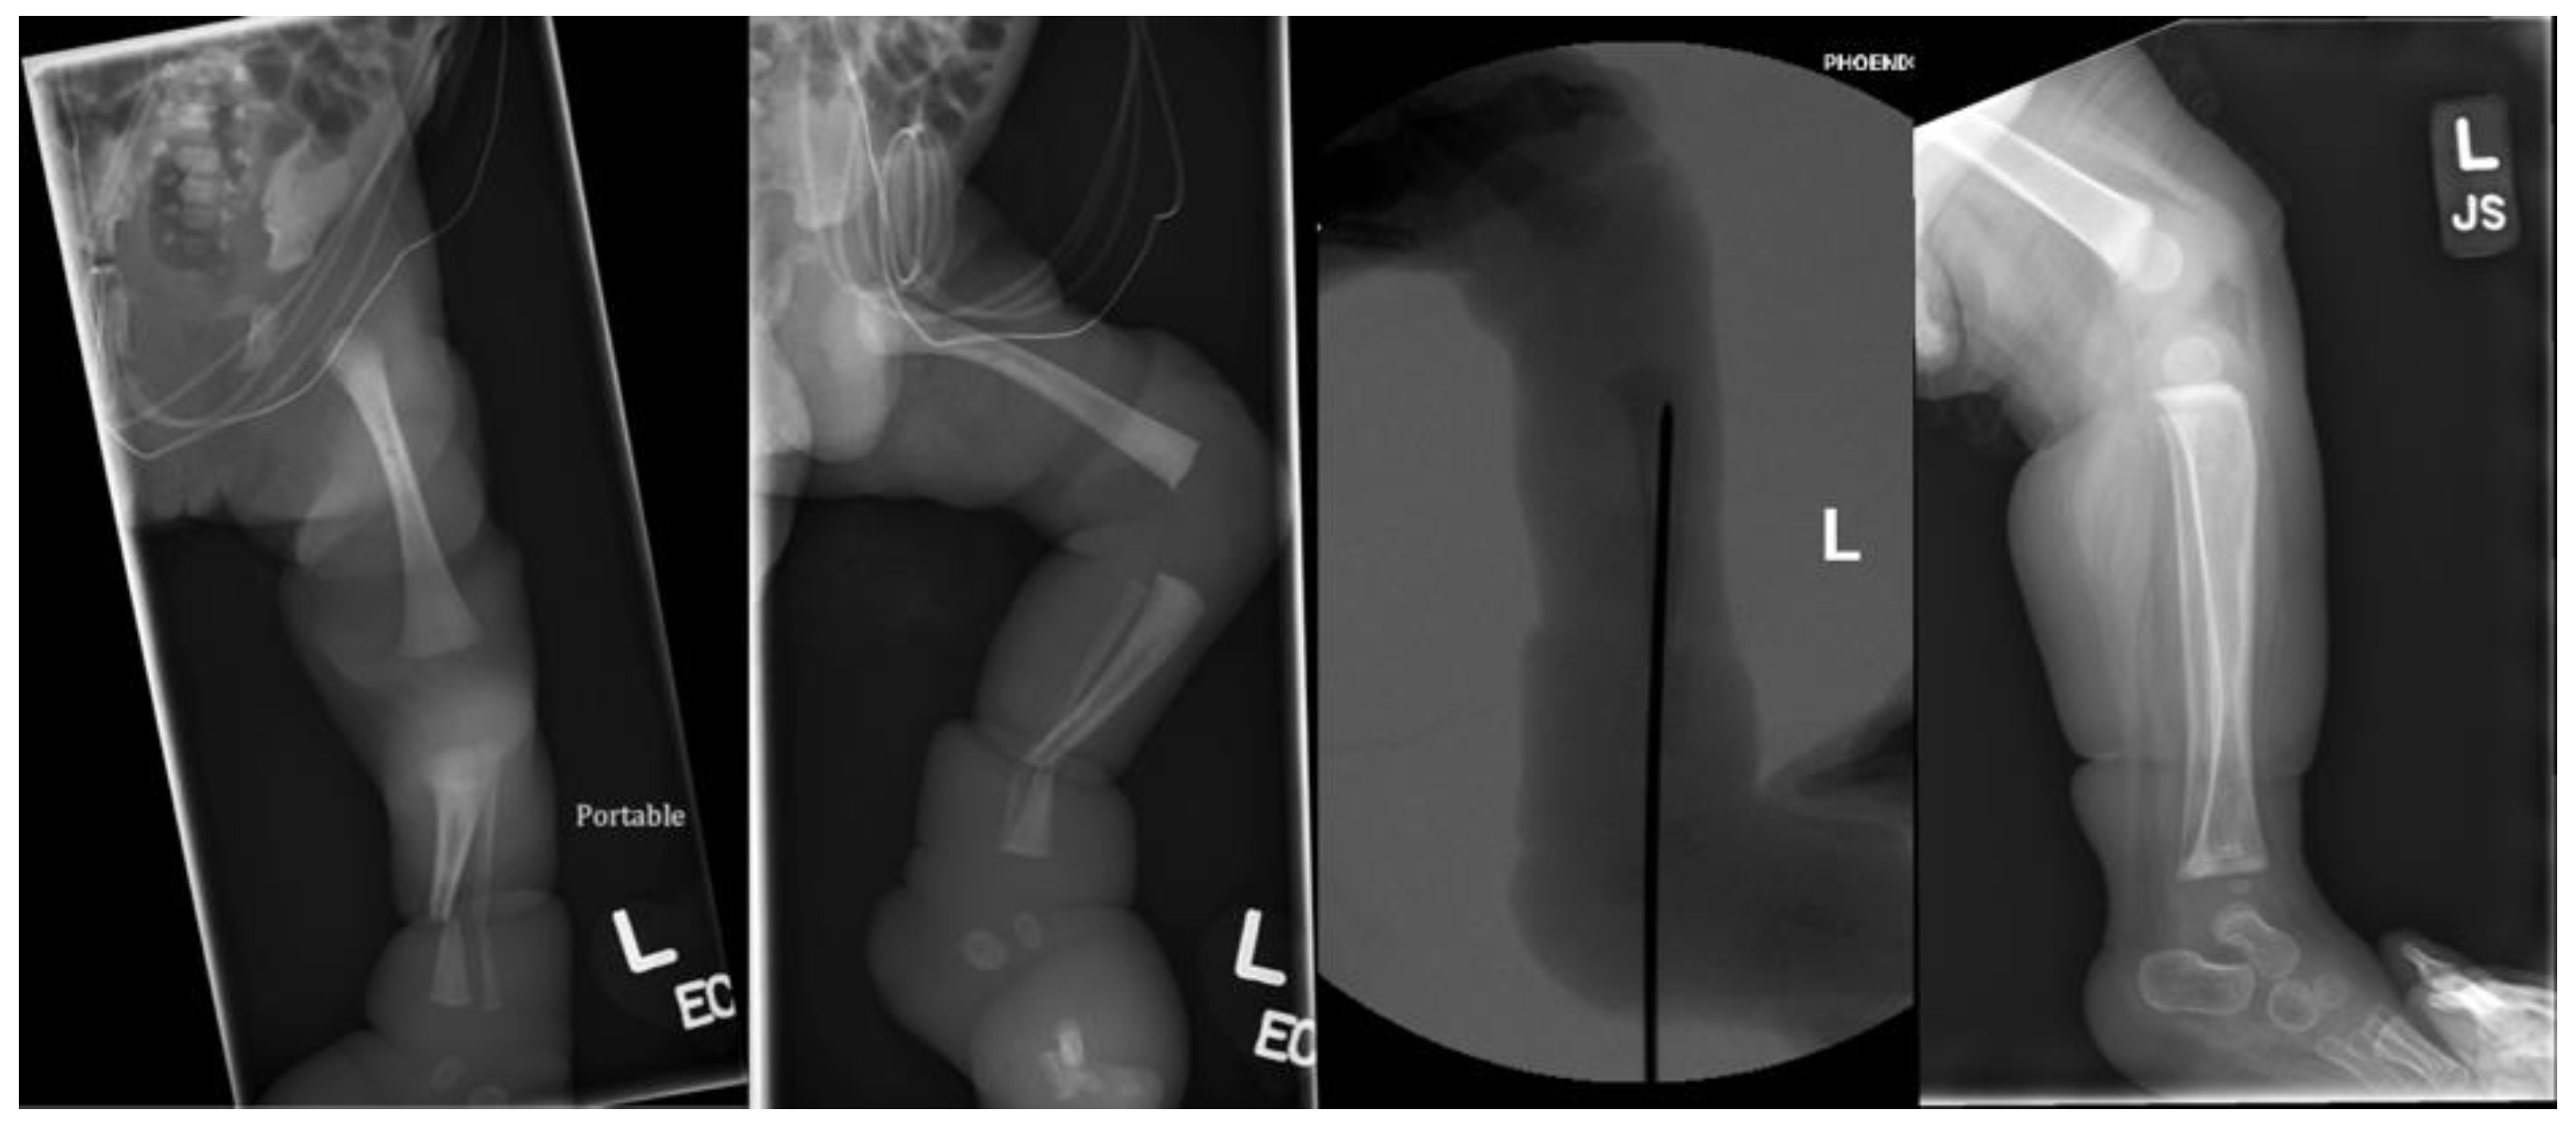

Fractures in the Setting of Constriction Band Syndrome: A Case Series of Three Patients with Extremity Fractures at the Site of a Constriction Band

2. Case Presentation